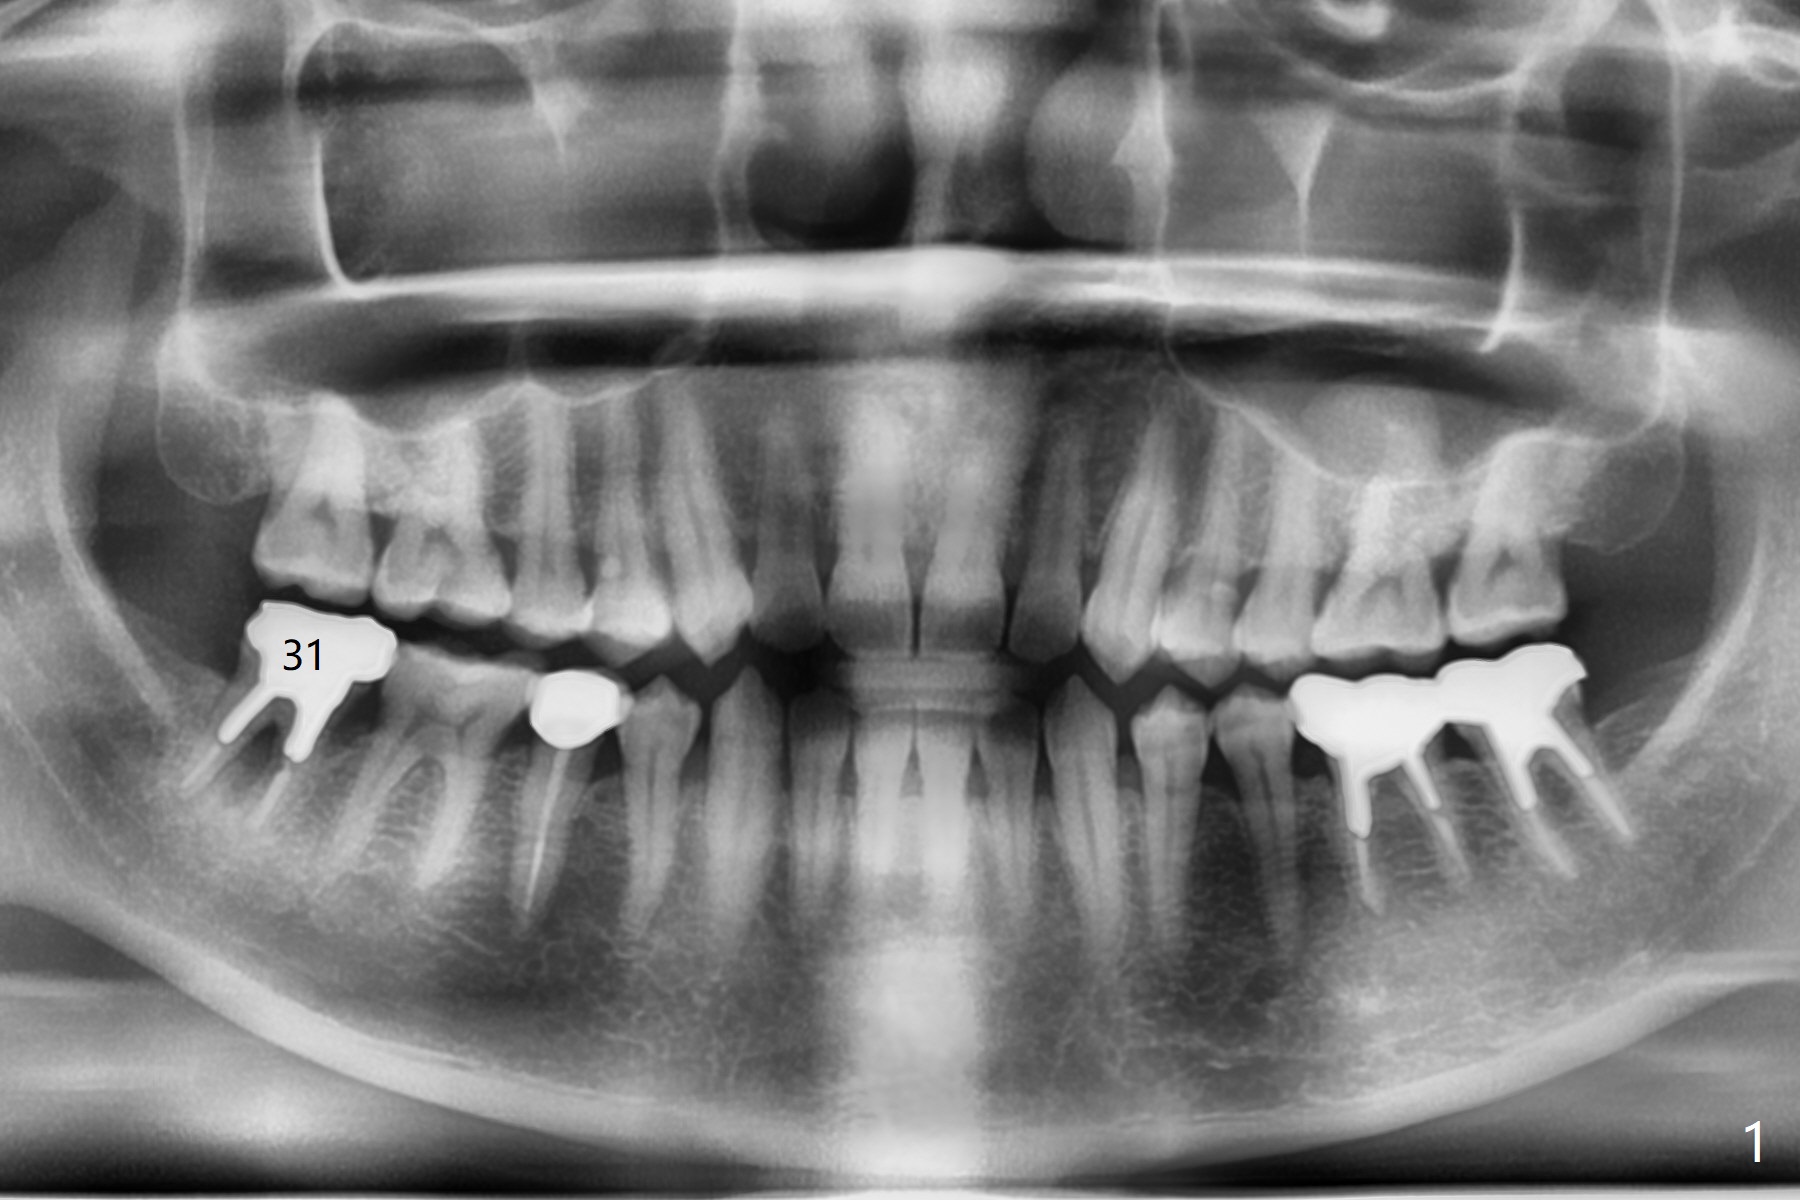

More Bone When Implant Placed in Mesial Socket

A 36-year-old woman has had an abscess and bone loss associated with the tooth #31 (Fig.1). It appears that there is less bone to support an implant when it is placed in the septum (Fig.2 S) than in the mesial socket (Fig.3 M).